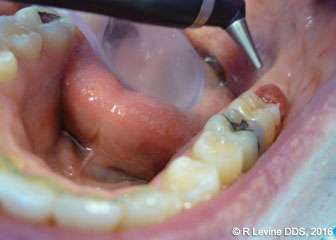

Figures 4A-4B, 5A-5B, 6A-6C, 7B-7C, and 8A demonstrate the enhanced hemostasis ensured by the LightScalpel CO2 laser. In Case 2, the patient had the vestibular extension procedure performed, and the hemorrhage was very well controlled, enabling the clinician with utmost precision. In Case 3, the bloodless excisional biopsy of fibroma was performed. Case 4 is a stage II implant uncovering procedure. This surgery requires both special accuracy and the well-controlled depth of laser energy penetration as well as enhanced hemostasis. No blood was present at any point. The implant was uncovered in approximately 30 seconds. In connection with implant uncovering, it should be mentioned that the recent study on the 10,600 nm CO2 laser removal of biofilm from titanium implant surfaces[11] reported that this laser wavelength does not affect titanium or titanium oxide (most common implant materials) and is therefore safe to use around implants. Case 5 shows a LightScalpel CO2 laser lingual frenectomy in a 7-year-old patient. Surgery is performed in a highly vascularized area where bleeding was well controlled. Finally, Case 6 is the ablation of the inflamed operculum. Figure 8A demonstrates the immediately postoperative view with excellent hemostasis.

Case 4: Stage II implant uncovering